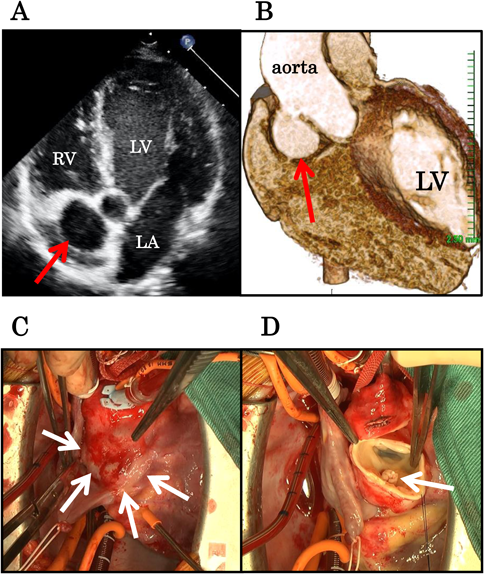

Fig. 1 Echocardiographic findings. Four-chamber view recorded during diastole showing the pseudoaneurysm (arrow) located anterior to the right atrium (A). Computed tomography (CT) with contrast enhancement image showing the aortic pseudoaneurysm (arrow) (B). Intraoperative photograph of the aortic pseudoaneurysm (arrows) (C). Intraoperative photograph of the vegetative growth (arrow) adjacent to the defect in the aortic wall (D)

LV; left ventricle, RV; right ventricle, LA; left atrium.

A 10-year-old boy was admitted to our hospital with fever of unknown origin. He had undergone percutaneous balloon aortic valvoplasty for congenital aortic valve stenosis when he was 2 years old. The initial pressure gradient at the aortic valve was 60 mmHg before valvoplasty. After percutaneous aortic valvoplasty, it decreased to 40 mmHg. The patient exhibited trivial aortic valve regurgitation. The balloon size was 95% of the aortic valve size. At the time of the current admission, his blood pressure was 100/60 mmHg; heart rate, 90 bpm; and respiratory rate, 16 breaths per minute. His body temperature was 38.0°C. Physical examination revealed a Levine-III/VI systolic-ejection murmur at the second right intercostal space. Laboratory investigations showed leukocytosis (14,000 cells/mm,3) 70% polymorphonuclear leukocytes), and his C-reactive protein level was elevated to 6.5 mg/dL. A chest radiograph showed no obvious signs of pneumonia or pulmonary congestion. Electrocardiography revealed sinus rhythm and no other abnormalities. The echocardiogram showed aortic valve stenosis, with a peak aortic pressure gradient of 40 mmHg. The parasternal long-axis view revealed vegetation attached to the aortic valve of the noncoronary cusp. We noted a thickened bicuspid aortic valve. Considering the size of vegetation, aortic valve stenosis was not caused by the vegetation. He was diagnosed with infective endocarditis of the aortic valve and treatment with aminobenzyl penicillin (200 mg/kg/day) for 6 weeks and intravenous gentamicin (3 mg/kg/day) for 2 weeks was initiated. Blood cultures obtained at the time of admission revealed the growth of Streptococcus mitis. After antibiotic administration, his body temperature returned to within the normal range 2 days after admission. However, echocardiography after antibiotic therapy showed an abnormal cavity near the ascending aorta (Fig. 1A). Although we performed echocardiography once per week during therapy, we did not detect the aneurysm until then. Contrast-enhanced computed tomography (CT) showed a defect in the right anterior wall of the ascending aorta, 5 mm above the aortic valve, and a pseudoaneurysm originating from the defect (Fig. 1B). Figures A and B are images obtained after 6 and 7 weeks of antibiotic treatment, respectively. The patient subsequently underwent ascending aortic replacement with a J graft (18 mm) to avoid rupturing the pseudoaneurysm 2 weeks after completing the antibiotic treatment. Intraoperative findings revealed a small amount of vegetation near the pseudoaneurysm entry-point (Fig. 1C, D); however, there was no sign of aortic valve infection. The postoperative course was uncomplicated, and the patient was discharged 4 weeks after the surgery.